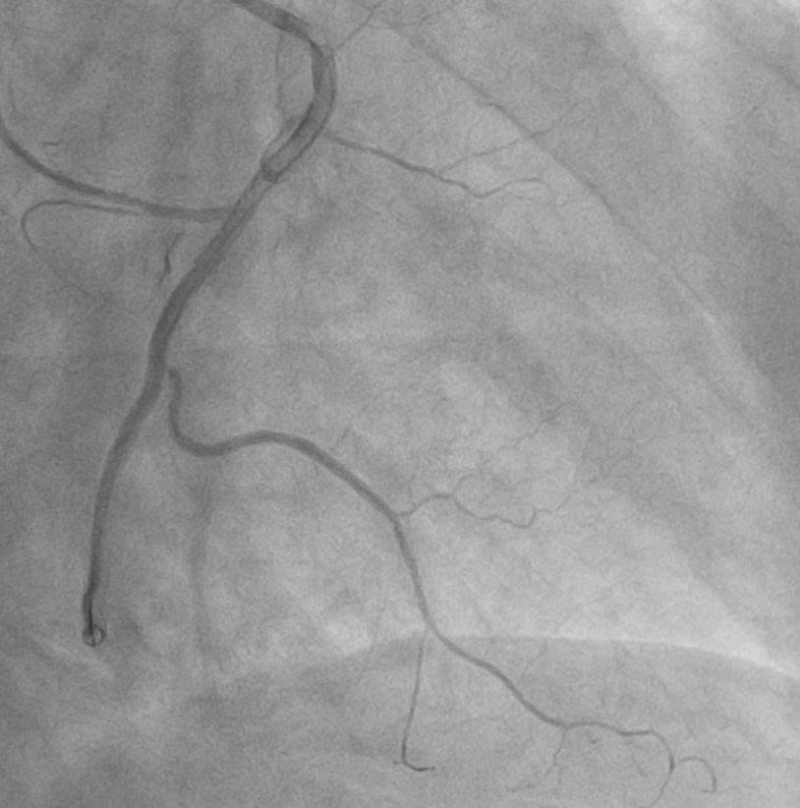

Ê-kíp can thiệp đã nhanh chóng triển khai nhiều biện pháp xử trí, trong đó có tiêm trực tiếp thuốc giãn mạch vào lòng động mạch vành như Adenosine nhằm giảm co thắt và cải thiện vi tuần hoàn. Sau khi xử trí tích cực, dòng chảy mạch vành đã được khôi phục với mức dòng chảy TIMI 2, giúp ổn định tình trạng cho người bệnh.

Hình ảnh: Sau can thiệp

Sau can thiệp, bệnh nhân được chuyển về khoa Tim mạch để tiếp tục theo dõi và điều trị. Đến sáng hôm sau, tình trạng sức khỏe bệnh nhân ổn định, tỉnh táo, giảm đau ngực, các chỉ số sinh tồn ổn định: mạch 69 lần/phút, huyết áp 120/80 mmHg, SpO₂ 99%, lượng nước tiểu đạt 3 lít trong 13 giờ.